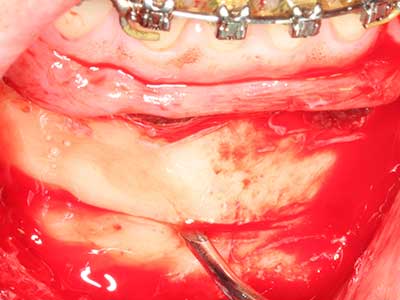

En la extracción de bloques óseos la piezocirugía también presenta ventajas adicionales: Además de la alta precisión en la osteotomía que ya se ha descrito antes, se ha comprobado que el uso de los delgados insertos de sierra resulta especialmente cuidadosas con el hueso. Frente a esto, sobre todo cuando se usan las fresas de Lindemann, cabe esperar pérdidas en la extracción significativamente más altas debido al mayor grosor de la parte frontal del cabezal (Lakshmiganthan, Gokulanathan et al. 2012). La separación basal que se necesita en particular en los injertos de bloque extraídos de forma retromolar se ve facilitada mediante sierras perpendiculares especialmente previstas a tal fin, lo que permite considerar que la cirugía piezoeléctrica es un procedimiento preciso y seguro para la obtención de bloques de hueso en el área retromolar (Happe 2007) (fig. 1-12).